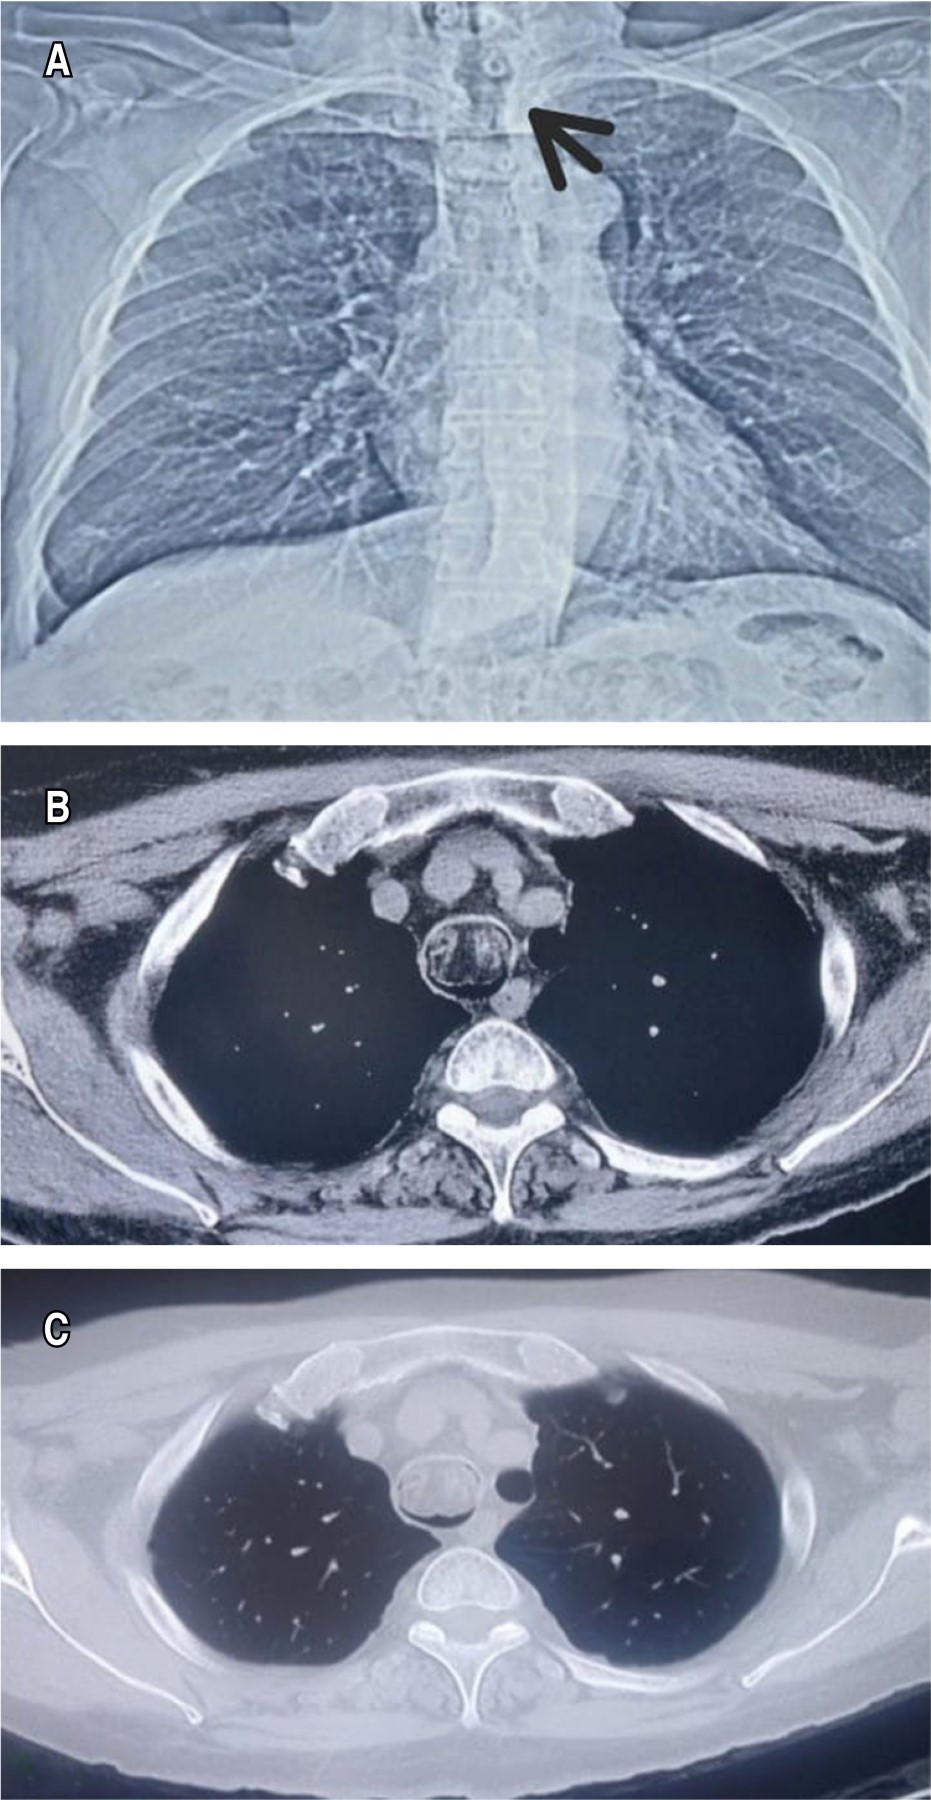

A 70-year-old man, with clinical picture of six months of evolution, characterized by dyspnea of medium efforts, progressing to small efforts and productive cough, with hyaline expectoration, not cyanosing or dyspneic. During the physical examination, vital signs: blood pressure (BP) 113/101 mmHg, HR 79 bpm, RR 22 rpm, temperature 36.2 °C, oxygen saturation 91% room air, initial arterial blood gasses pH 7.45, PCO2 36.7 mmHg, PO2 65 mmHg, with stridor, no evidence of respiratory distress, bilateral rales were auscultated in the lung fields. Oxygen was administered through nasal prongs at two liters with oxygen saturation at 94%. Chest X-ray was performed without parenchymal alterations, with an image of tracheal stenosis (Figure 1A). A simple chest CT scan was requested, showing an irregular encapsulated lesion adhered to the anterolateral wall of the middle third of the trachea (Figures 1Band 1C). Fibrobronchoscopy was performed (Figure 2A), and a 3 × 2 cm whitish tumor was identified at the level of the sixth tracheal ring obstructing 95% of its pedunculated tracheal lumen in the anterior wall. Resection was performed by rigid bronchoscopy and total resection of the tumor (Figure 2B). Histopathological examination reported tracheal lipoma (Figures 2C and 2D). The patient presented good evolution with no data of respiratory compromise. He was discharged due to improvement, with tomographic follow-up one month after the procedure without evidence of recurrence, with adequate patency of the tracheal lumen.

Commonly, it is difficult to find a lesion on a conventional chest radiography because the trachea is covered by the mediastinum, almost always seen as normal, as in this case (Figure 1).1-3 Studies such as CT and flexible bronchoscopy are valuable for diagnosis, which were performed in our case.1-3